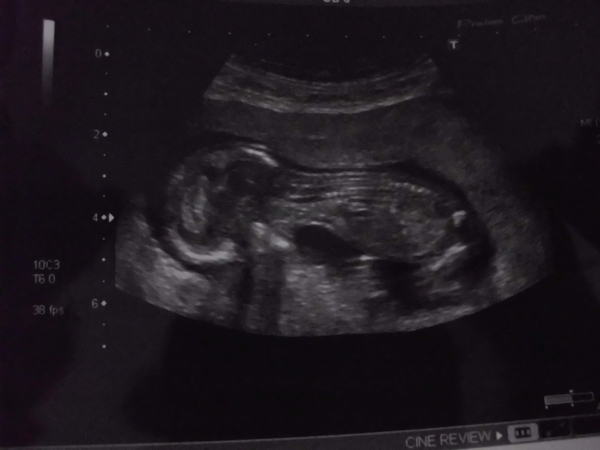

Here is my 13 week scan i'm not sure if you can see a nub as i have no idea what i'm looking for. I don't mind what sex the baby is but secrectly i'm kinda hoping for a girl as i already have two boys. Daddy wants a boy though as this is his first baby. Any guesses would be amazing. thankyou :) xAttachment 6357